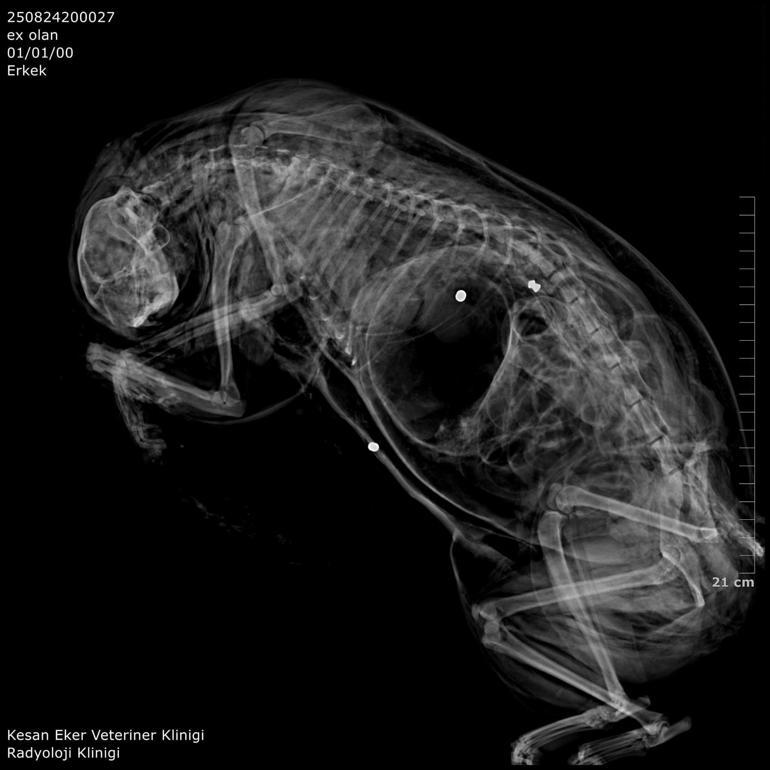

Hüseyin Bülbül ayrıca ölü bulunan kedileri özel bir kliniğe götürdü. Klinik raporunda, 'ateşli silah yaralanması ile uyumlu patolojiler' tespit edildiği, hayvanların tüfek saçması sonucu öldüğüne ilişkin bulgulara yer verildi. Bülbül, güvenlik kamerası görüntülerinden komşusu K.G.'den şüphelendi. Görüntülerde; K.G.'nin bahçesine giren bazı kedilerin aniden kaçtığını fark etti.

İpsala Cumhuriyet Başsavcılığı'nın olaya ilişkin hazırladığı iddianamede K.G., hakkında, 'Bir ev hayvanını veya evcil hayvanı kasten öldürme' suçundan 6 aydan 3 yıla kadar hapis cezası istendi. İddianamede, "Herhangi bir silah ateşleme görüntüsü tespit edilmese de şüphelinin ikamet ettiği evin bahçe kapısı önünde bir kedinin can çekiştiği ve bir kedinin de kaçtığının tespit edildiği, dosya kapsamında tanık olarak beyanı alınan S.Ç.'nin şüphelinin bahçe kapısı önünde bir kediyi yatar vaziyette gördüğünü, başını sevmek istediğinde kedinin ölü olduğunu fark ettiğini, kediyi eline aldığında başından kan aktığını görmesi üzerine yol üzerinde kalmaması amacıyla kediyi çöp tenekesinin içerisine bıraktığını, ölen ve yaralanan 2 kedi hakkında düzenlenen 25/08/2025 tarihli veteriner hekim ön muayene raporu ile çekilen radyografilerde ateşli silah yaralanması (kuş saçması) ile uyumlu patolojiler gözlemlendiği şeklinde rapor tanzim edildi. Tüm dosya kapsamı incelenmekle şüpheli savunması, bilgi sahibi beyanları, İpsala İlçe Tarım Müdürlüğü'nün yazılı başvurusu, müşteki beyanı, kamera görüntüleri ve kriminal raporları birlikte değerlendirildiğinde, şüphelinin olay tarihinde müşteki Hüseyin Bülbül tarafından da beslenmekte olan sokak kedilerine ateş etmek suretiyle, bir kedinin ölümüne neden olarak üzerine atılı suçu işlediğine dair ve bir kedinin yaralanmasına neden olarak tariflenen suçu işlediğine dair hakkında kamu davası açmak üzere yeterli şüphe oluşturacak kadar delilin mevcut olduğu anlaşılmakla" denildi.

Hüseyin Bülbül'ün avukatı Edirne Barosu Keşan Temsilcisi ve Hayvan Hakları Komisyonu Başkanı Büşra Ağır Ürkmez, kedilerin 2018 yılından bu yana sistematik olarak öldürüldüğünü belirterek, "En somut adımlar, 24 Ağustos 2025 tarihiyle Hüseyin Bülbül'ün şikayet etmesi neticesinde başlamıştır. Davanın ilk celsesi görüldü. İlk celsede deliller toplandı. Balistik rapor sonucu dosyaya ibraz edilmiştir. Şüpheli beyanlarında suçu işlemediğini, bu olayla ilgi ve alakasının olmadığını söylemişse de dosyadaki mevcut deliller, tanık beyanları şüphelinin ifadelerinin gerçeği yansıtmadığını ortaya çıkarmaktadır. Bu konuyla ilgili olarak davanın takipçisi olacağız" dedi.

K.G.'nin kedileri bahçesinde ateşli silah ile vurduğunu belirten Ürkmez, "Bununla ilgili delillerimizi dosyayla sunmuş bulunmaktayız. Onun haricinde veteriner ön raporunda da kedilerin ölümüyle ilgili olarak vücutlarında saçma bulunduğu açıklığa kavuşmuştur. Kamera kayıtlarımızı da delil olarak dosyayla sunduk. Bu konunun takipçisiyiz. '5199 sayılı Hayvan Haklarını Koruma Kanunu gereği de şüphelinin ceza alması için elimizden gelen her şeyi baro olarak yapmak niyetindeyiz. Bununla ilgili son kararı mahkeme verecektir. Şüphelinin yurt dışına çıkış yasağı ve adli kontrolü ise devam etmektedir" diye konuştu. Hüseyin Bülbül ise davanın sonuna kadar takipçisi olacaklarını kaydederek, K.G.'nin hak ettiği cezayı almasını istediklerini söyledi. (DHA)